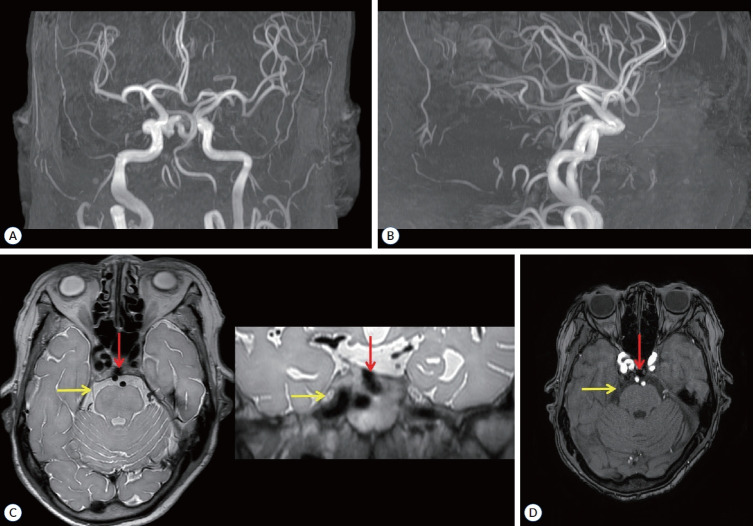

Persistent trigeminal artery (PTA) is the most common residual manifestation of persistent carotid-vertebrobasilar anastomosis, with the medial-type (intrasellar or sphenoidal) PTA being exceptionally rare. Aneurysms originating from the PTA trunk are not common. We present a unique case of an aneurysm located at the trunk of the medial-type PTA in a patient presenting with trigeminal neuralgia who successfully managed by endovascular procedure. Furthermore, we discuss the anatomical features of this aneurysm and relevant reports, and examine the possible pathomechanism of the associated pain.

Abstract Image